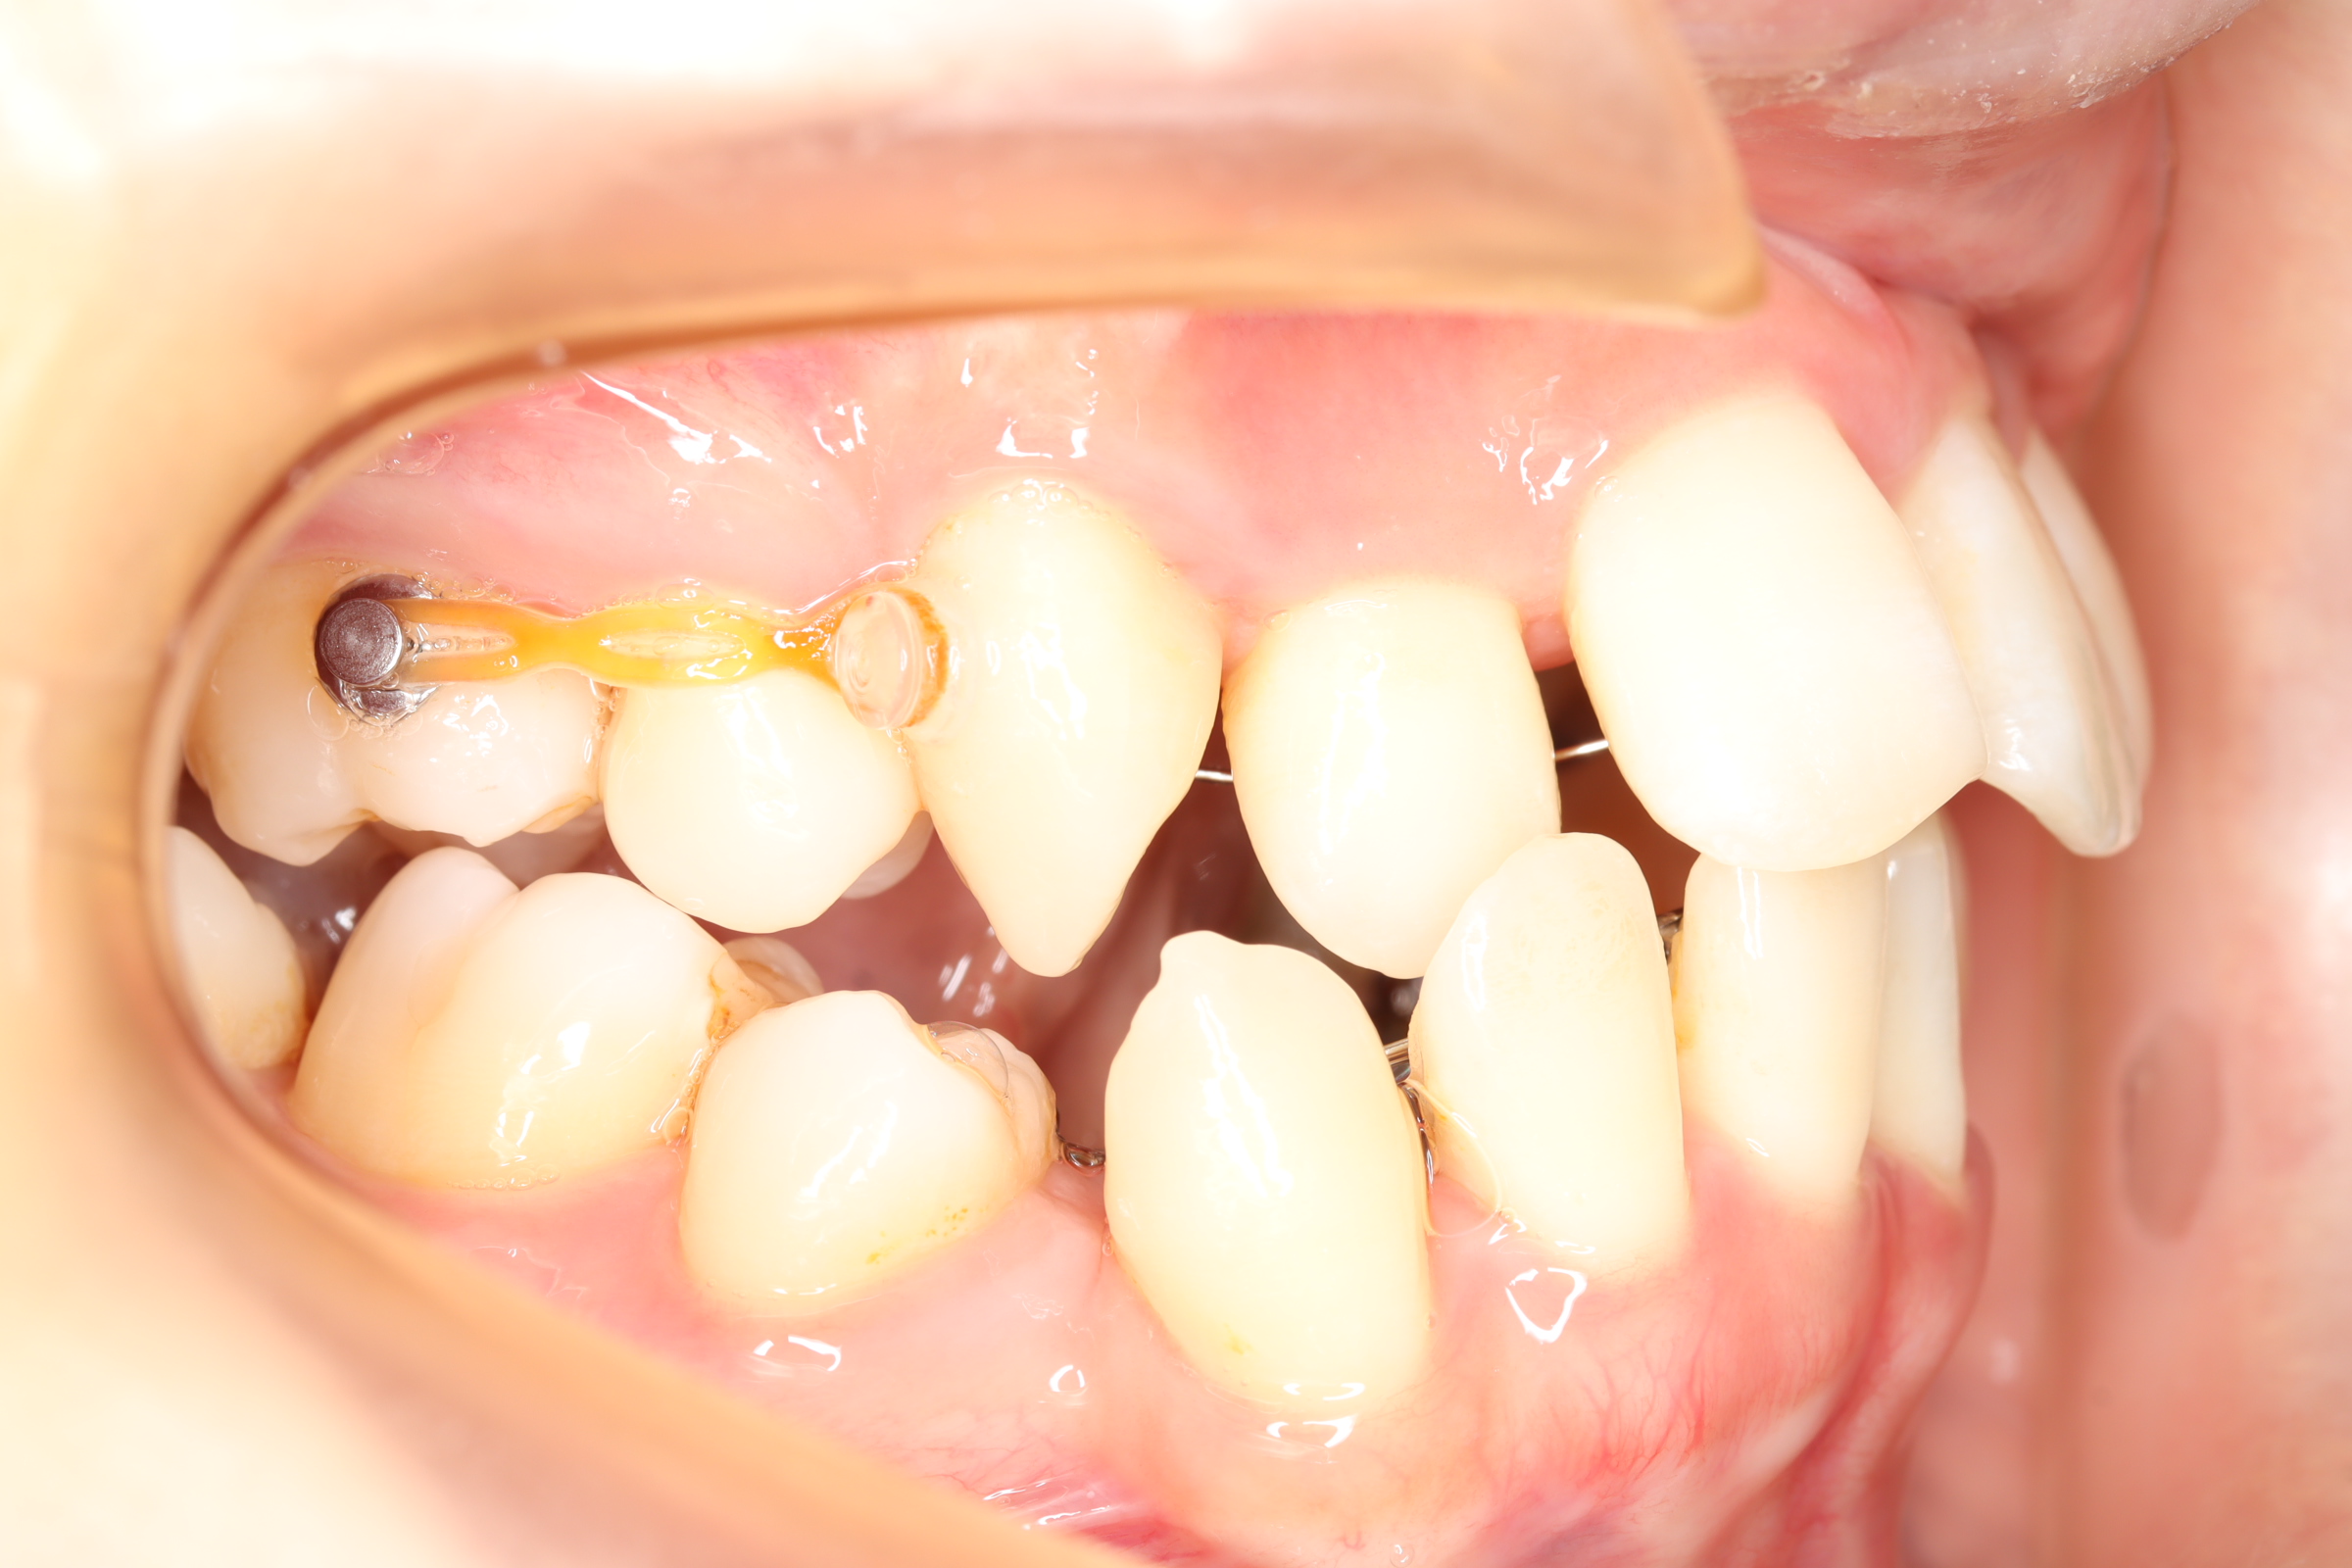

治療中

| 抜歯の有無 | 上下顎両側第一小臼歯(前から4番目の歯) |

| 使用矯正装置 | セルフライゲーションリンガルブラケット 歯科矯正用アンカースクリュー |